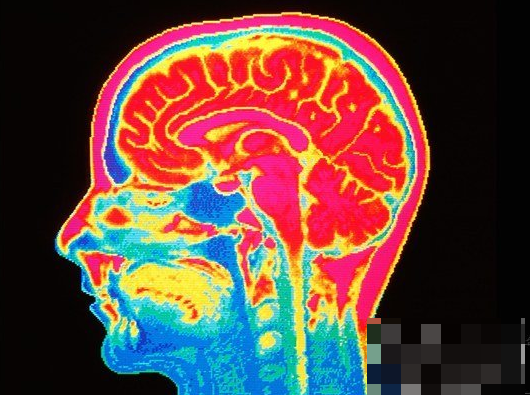

功能磁共振成像扫描了两组人对“死亡”一词的思考。左边的是有自杀倾向的人。右边是控制组。